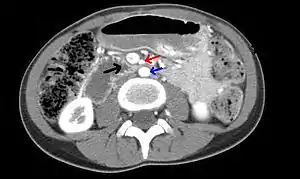

| Abdominal and pelvic computed tomography scan showing duodenal compression (black arrow) by the superior mesenteric artery (red arrow) and the abdominal aorta (blue arrow). | |

Diagnosis is very difficult, and usually one of exclusion. SMA syndrome is thus considered only after patients have undergone an extensive evaluation of their gastrointestinal tract including upper endoscopy, and evaluation for various malabsorptive, ulcerative and inflammatory instestinal conditions with a higher diagnostic frequency. Diagnosis may follow X-ray examination revealing duodenal dilation followed by abrupt constriction proximal to the overlying SMA, as well as a delay in transit of four to six hours through the gastroduodenal region. Standard diagnostic exams include abdominal and pelvic computed tomography (CT) scan with oral and IV contrast, upper gastrointestinal series (UGI), and, for equivocal cases, hypotonic duodenography. In addition, vascular imaging studies such as ultrasound and contrast angiography may be used to indicate increased bloodflow velocity through the SMA or a narrowed SMA angle.[12][13]